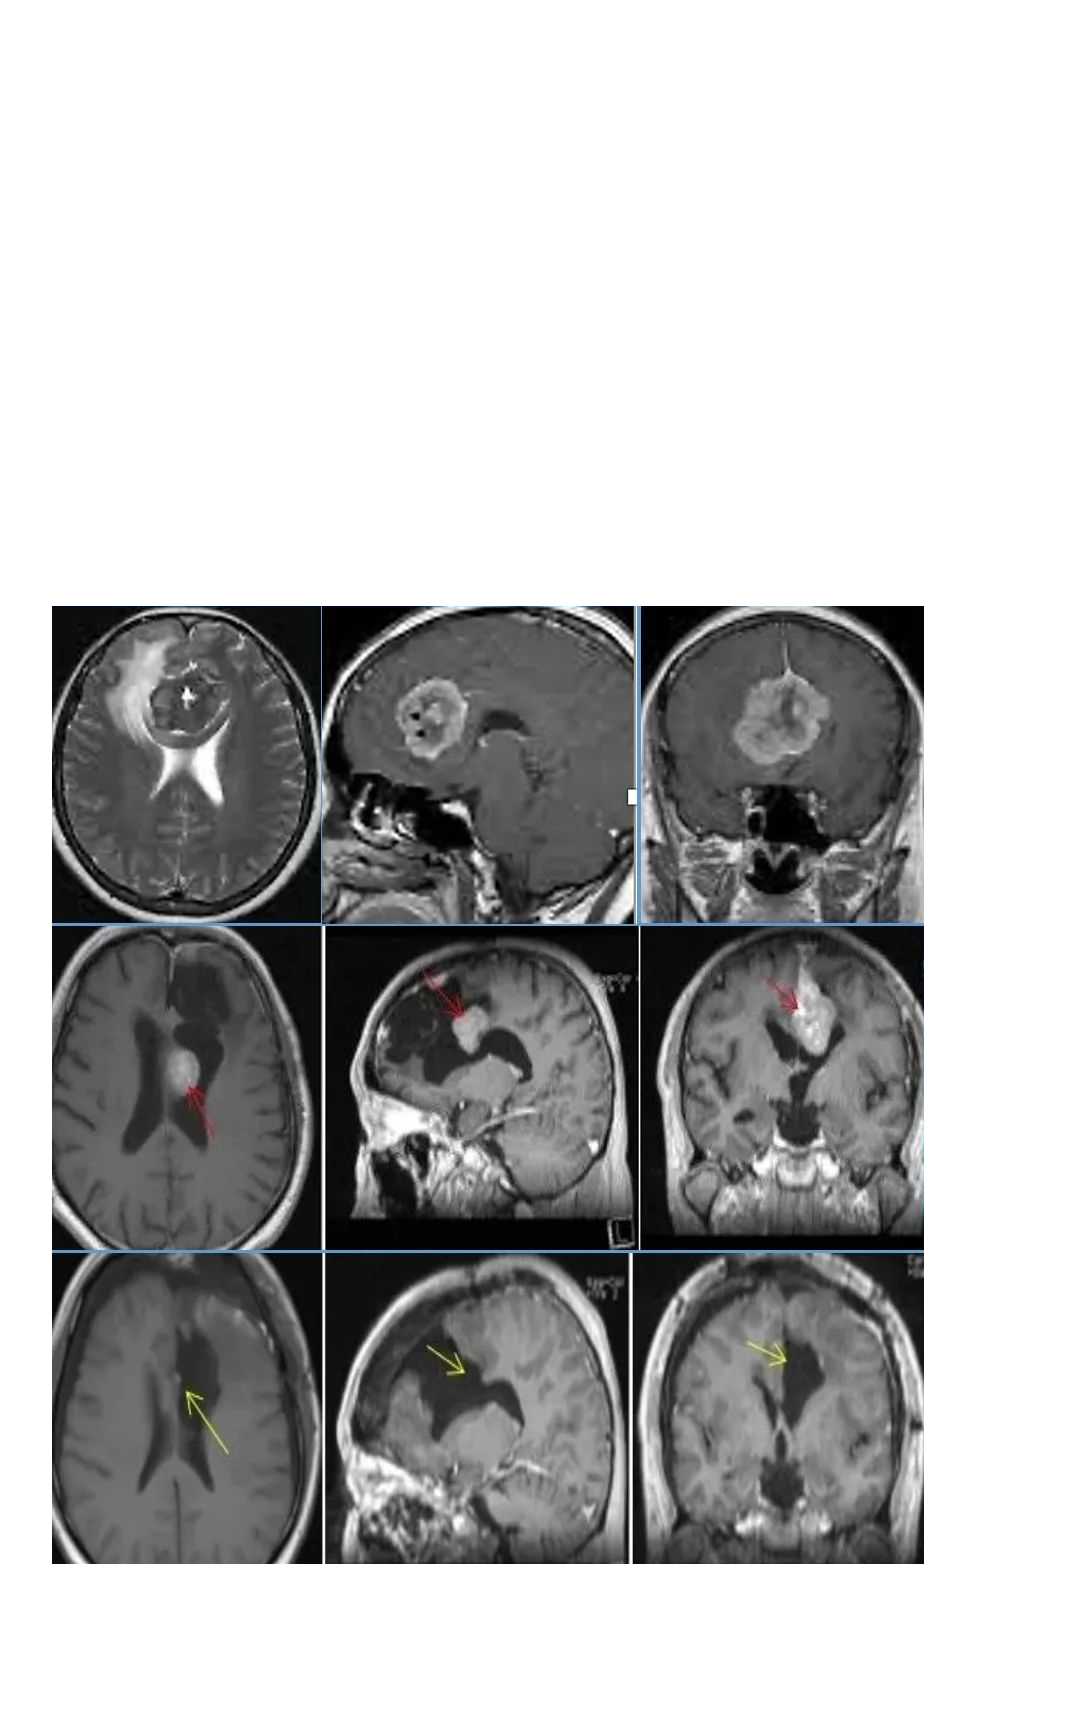

关于手术作为单一治疗的合适性的证据

来自于医疗机构的病例系列

确定了切除范围(EOR)是一个重要的预后因素

这方面常仍然使用Simpson分类

图:现国际通行的Simpson分级评估脑膜瘤复发的关系